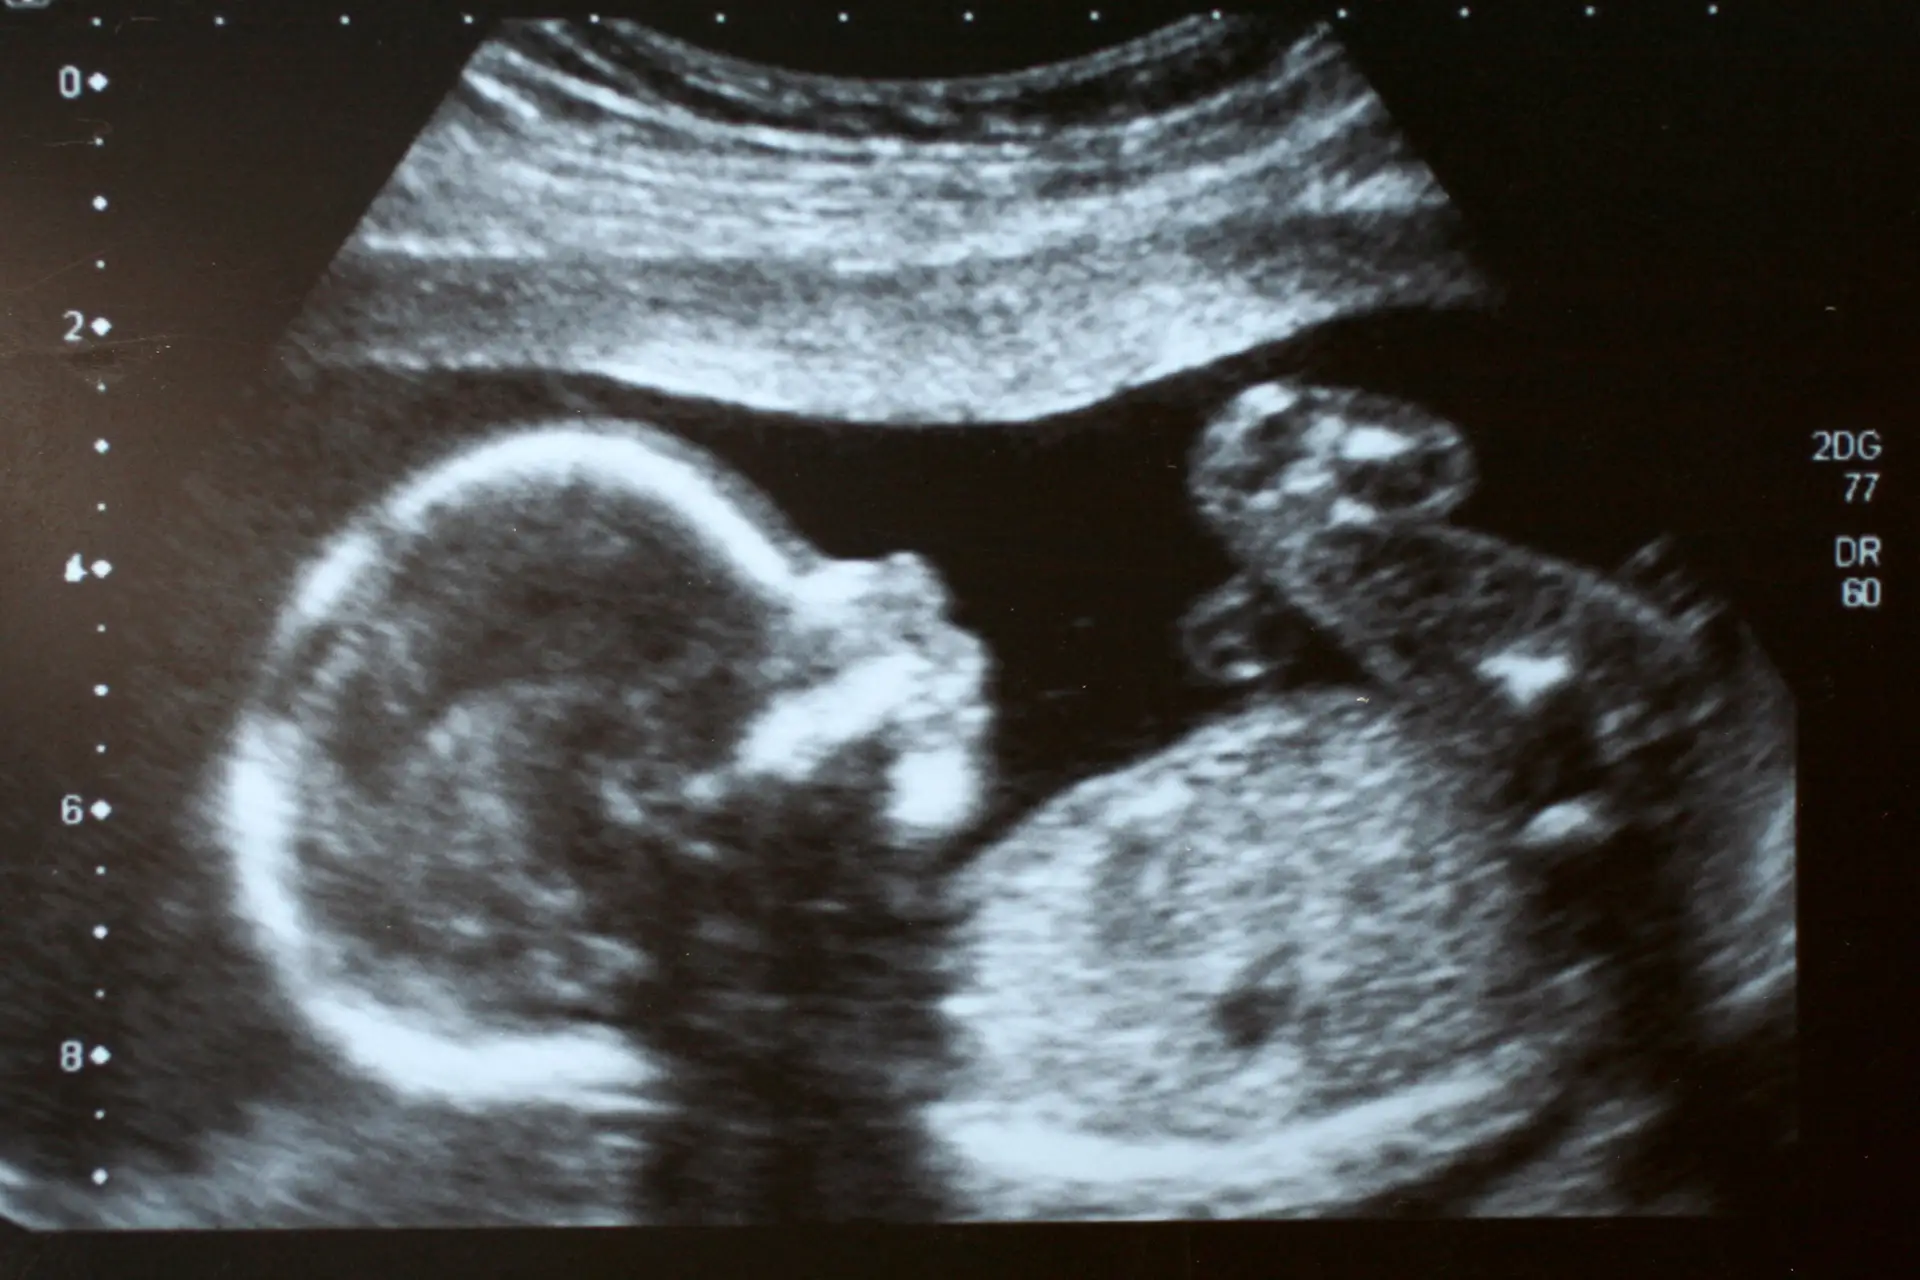

Badania 3D i 4D przebiegają podobnie do badań tradycyjnych. W czasie badania 3D dziecko jest widoczne na ekranie monitora w trzech wymiarach jako nieruchoma bryła. W przypadku badania 4D otrzymujemy obraz ruchomy – widzimy dziecko, które się rusza, obraca. Różnica polega więc na tym, że otrzymujemy albo trójwymiarowe zdjęcie, albo nagranie wideo.

Badanie 3D/4D zapewniają rodzicom możliwość zobaczenia twarzy i uśmiechu dziecka, jego całego ciała prawie tak, jak widoczne byłoby na zdjęciu. Przyczynia się to do komfortu psychicznego rodziców, którzy widzą prawidłowo rozwijające się dziecko. Rodzice mogą „na żywo” obserwować ruchy dziecka, mogą ten zapis również otrzymać na dyskietce DVD i odtworzyć nagranie w dowolnym czasie w domu. Dzięki temu badanie USG 3/4D jest nie tylko badaniem profilaktycznym, ale również pamiątką, która buduje więź z dzieckiem i między rodzicami.